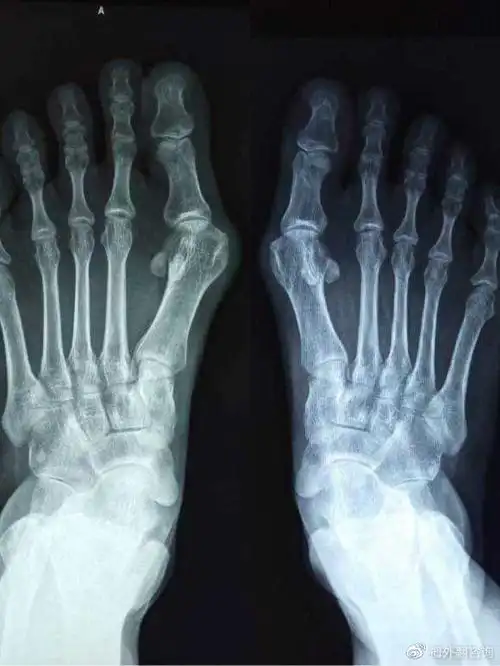

大脚骨一阵一阵的疼痛原因是什么?医生教你缓解和治疗

大脚拐,大脚趾内侧疼痛,要警惕:拇(趾)外翻,拇囊炎

大脚骨的病因及临床表现

大脚骨有哪些明显症状